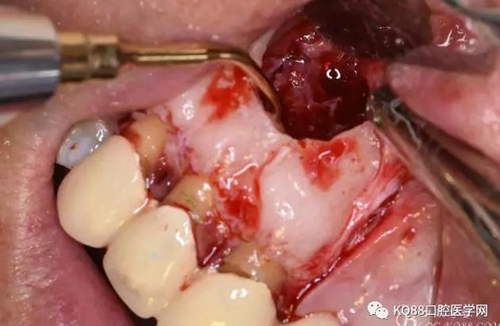

圖10.剝離囊壁

圖11.摘除囊壁后形成的骨腔